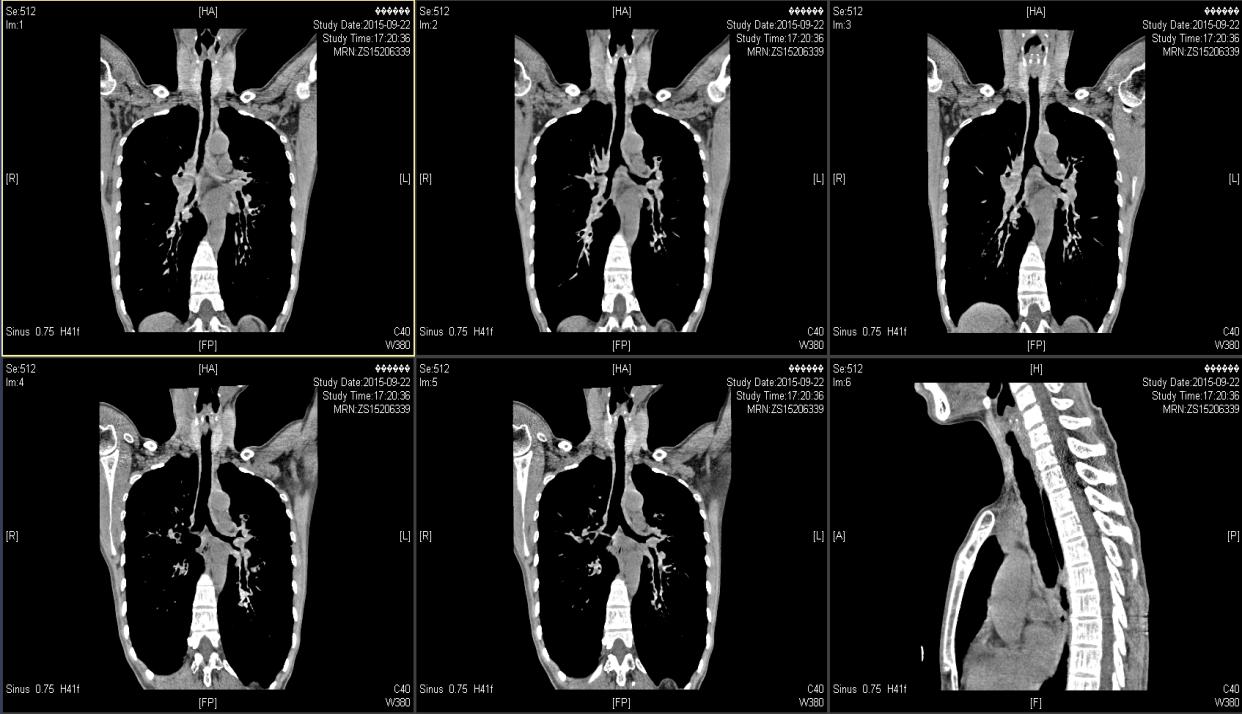

( 2015-9-22 ) 我院气管三维重建CT示 :气管、主支气管及其分支形态欠规则,管壁见明显增厚,管腔内壁凹凸欠光整,肺门处支气管管壁明显增厚,可见少许钙化,肺门处支气管管腔局部狭窄,远端分支管腔扩张呈囊柱状。见图1—图4。

图3

图4